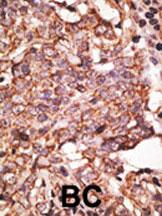

Formalin-fixed and paraffin-embedded human cancer tissue reacted with the primary antibody, which was peroxidase-conjugated to the secondary antibody, followed by AEC staining. This data demonstrates the use of this antibody for immunohistochemistry; clinical relevance has not been evaluated. BC = breast carcinoma; HC = hepatocarcinoma.